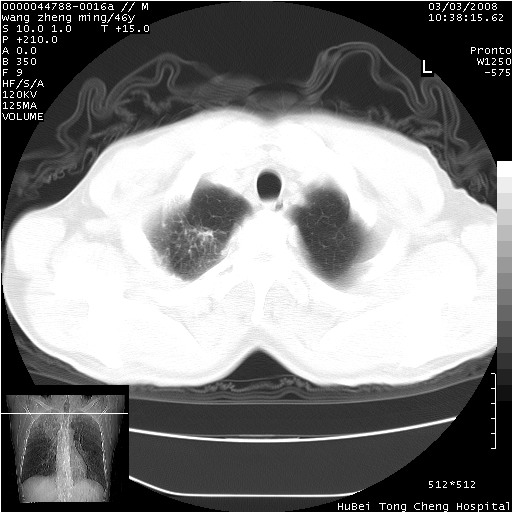

以下是引用卜一在2008-3-22 1:37:00的发言:[br]右肺实质性肿块,边缘不整,明显见毛刺征 分叶征及胸膜凹陷征,右上叶支气管明显变窄,远端散在的片状 斑片状实变影。另:左肺门较大肿块,支气管受累 变窄,远侧见阻塞性肺炎。纵隔内见肿大淋巴结。多考虑:右肺周围性肺癌伴左肺门 纵隔淋巴结转移!